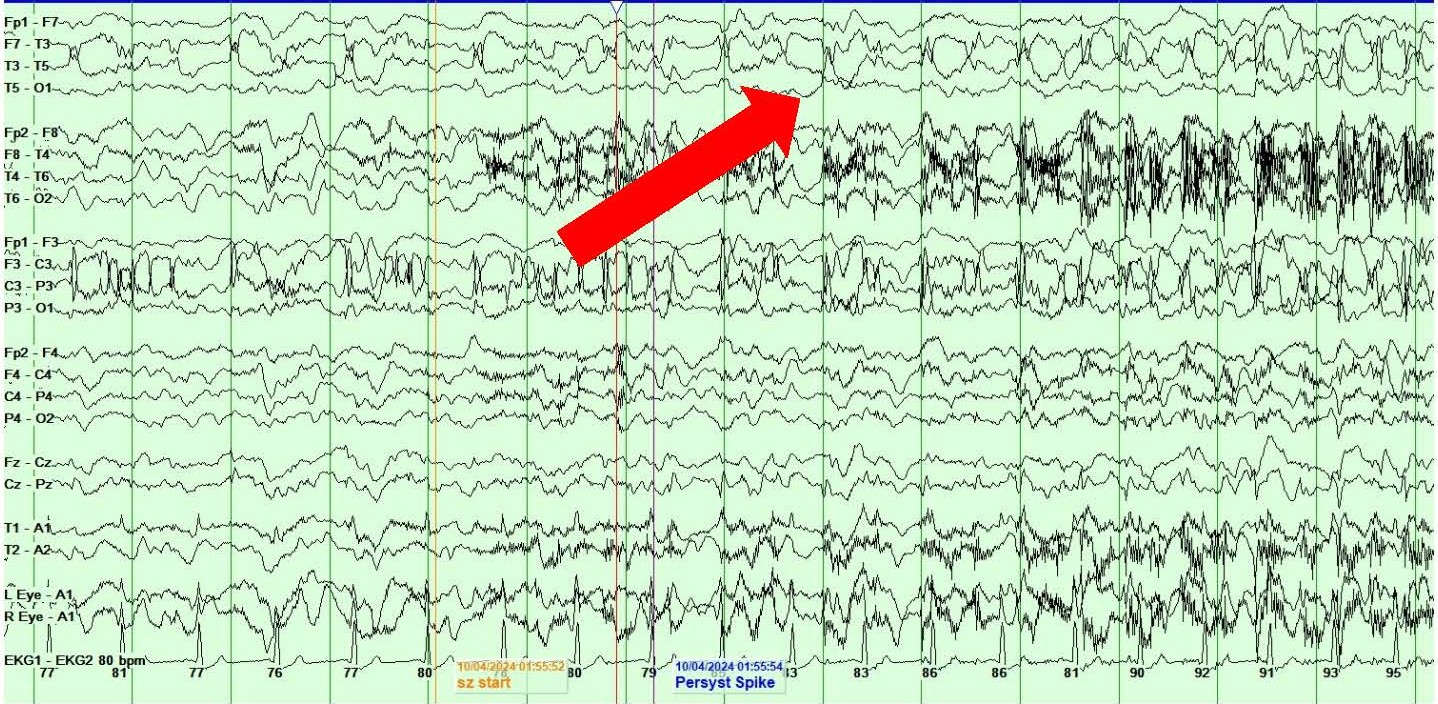

She also showed the presence of right hemispheric LPDs at 1-2 Hz and LRDA at 2-3 Hz that lasted for 1-10 minutes and occurred consistently with stimulation during physical manipulation or care by the medical providers and nursing staff (Figures 4A and 4B). These findings occurred independent of the previously described left hemispheric onset seizures mentioned above. They were felt to represent SIRPIDs (SI-LPDs and SI-LRDA).

Figures 4. A, B) Screenshots from Video EEG showing RIGHT hemispheric SIRPIDs provoked by stimulation (SI-LRDA and SI-LPDs) (marked by red arrows).